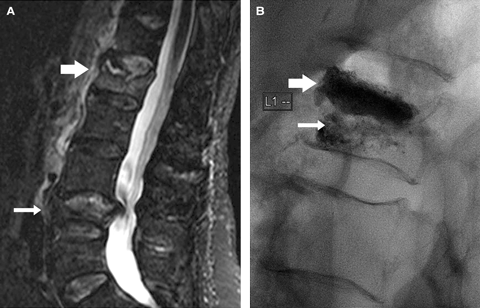

Most of the fractures that we treat are not simple crush fractures, but have more complex architecture. These more complex fracture types are associated with more severe pain. Axial transections of the vertebral body (Box 1) seem far more painful than simple crush fractures. Acute fractures adjacent to old, deformed, healed fractures are also associated with amplified pain, presumably because there is abnormal biomechanical stress through the fracture line. Osteonecrotic fracture clefts develop in some patients with osteoporosis (Box 2), and are often associated with severe and more prolonged pain. We observe that vertebroplasty provides early pain relief and mobilisation in patients struggling to cope in the acute situation.